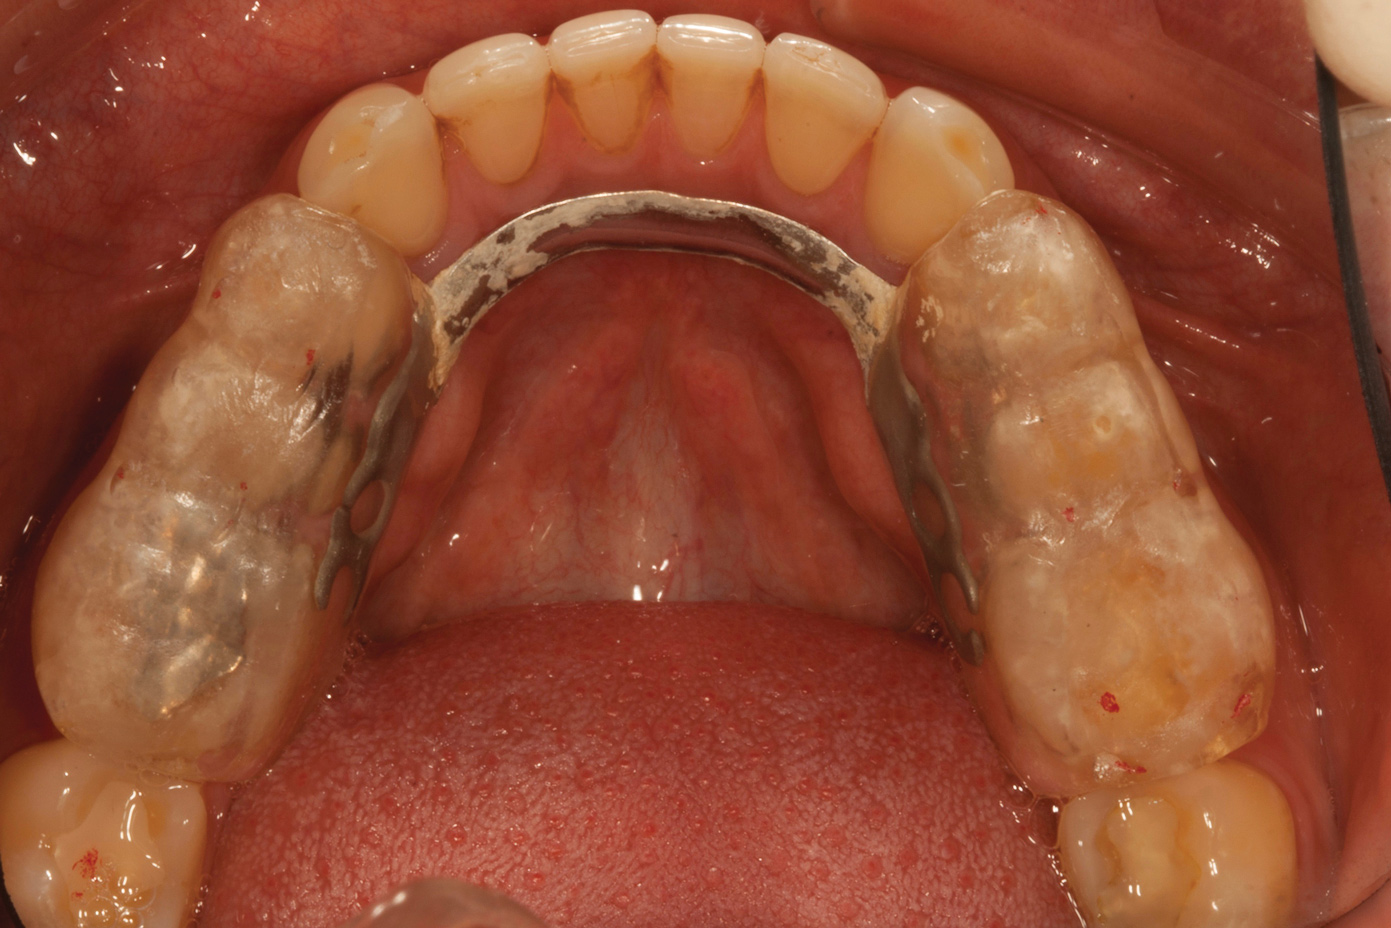

Over time, the patient had developed joint and muscle symptoms due to his lack of posterior support and sought the help of a specialist. His bite was analyzed, and he was fitted with a dental orthotic that allowed his teeth to touch in centric relation (Figure 3). This was intended to be a temporary measure to stabilize the patient's bite and make him comfortable, but before any permanent treatment could be carried out, he moved abroad and had been living with the device for more than 4 years before the time of the consultation. He stated that his bite was now very stable with the orthotic, but he was looking for a more permanent solution and also wanted to improve the overall appearance of his smile.

The patient's removable dental orthotic covered the lower bicuspids and first molars. With the orthotic in place, there was shim stock contact on all posterior teeth and on the second molars that were not covered by the appliance. However, there was no incisal overlap and a lack of anterior guidance.9When the orthotic was removed, no more than three teeth touched, and a 2-mm space between the posterior teeth made mastication difficult.

Fig 3. Preoperative occlusal view of lower arch with orthotic in place.

Figure 3